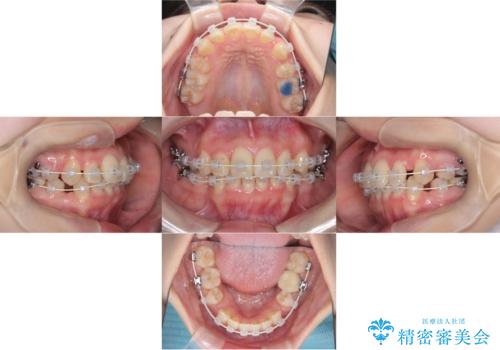

- 「歯のデコボコ、八重歯、口ボコが気になる」を主訴に来院された患者様です。

上下左右4番(4本)の歯を抜歯しワイヤー矯正で治療を行いました。

計4本の抜歯を行い、歯のデコボコと口元がすっきりし、大変ご満足していただけました。